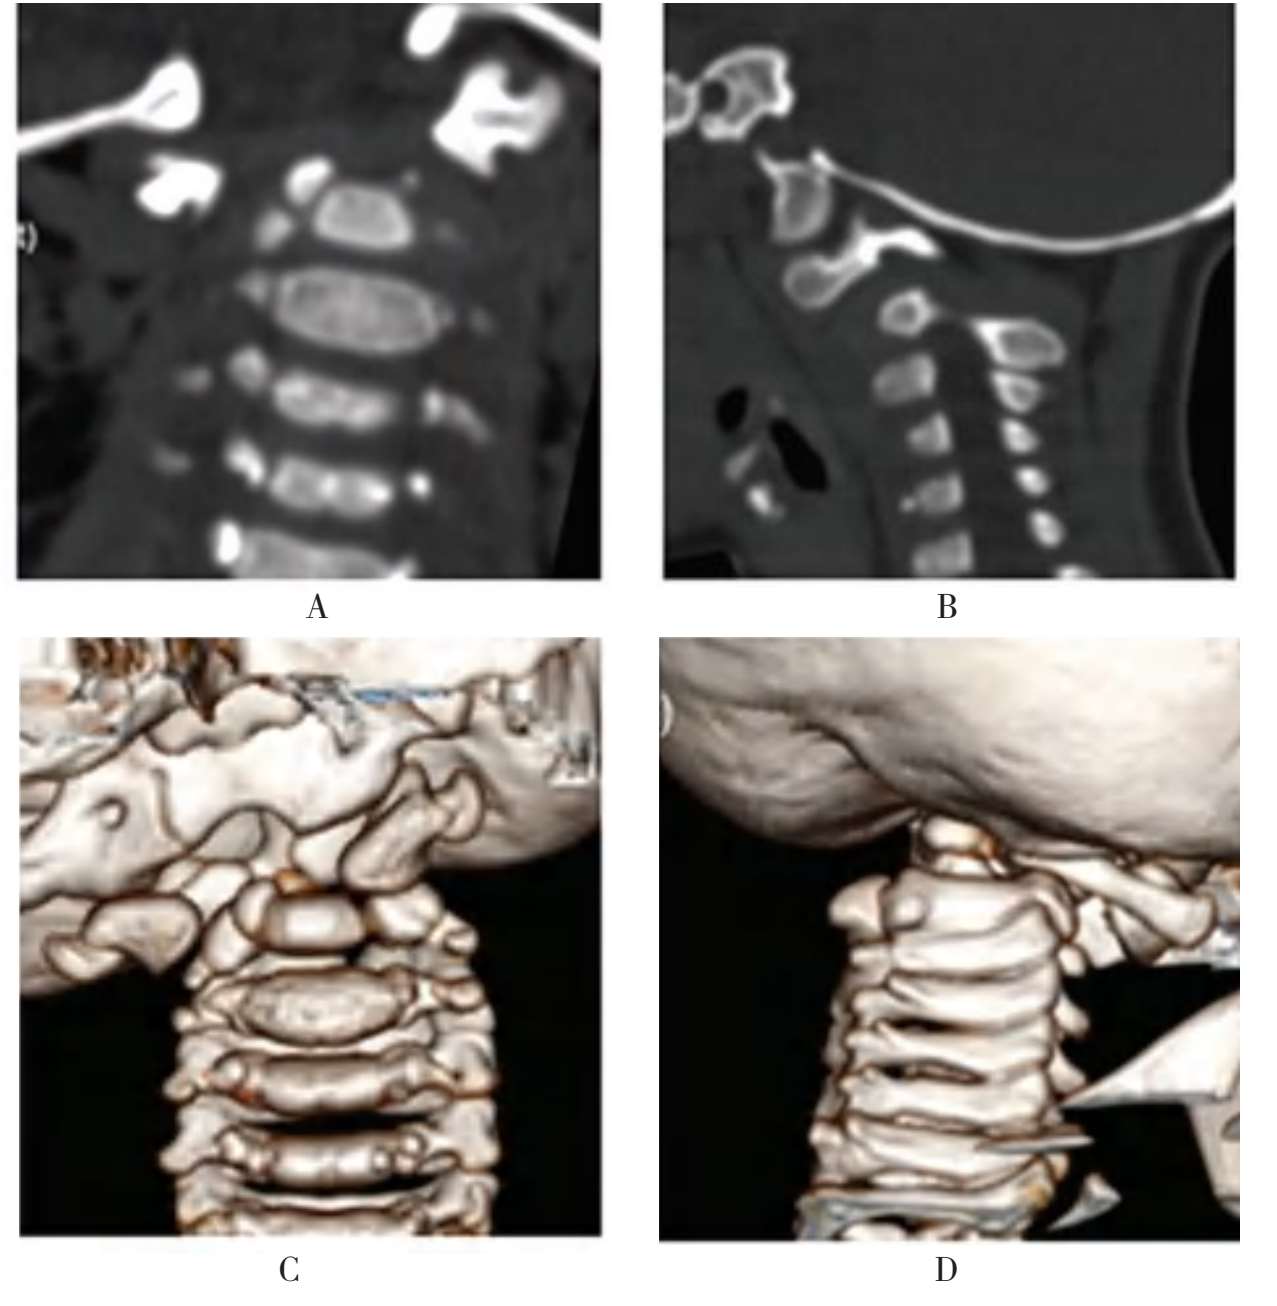

患儿,女,6岁11个月,不明原因颈痛、头颈歪斜,活动受限,伴一侧上肢疼痛麻木,走路不稳1年,加重3个月收治入院(图1-32A至图1-32C)。

患儿的颈椎CT检查提示:枢椎游离齿状突,寰椎后弓发育不良,寰枢椎脱位。

颈椎MRI检查提示:寰枢椎脱位,高位颈脊髓明显受压,变细。诊断:枢椎游离齿状突伴寰枢椎脱位。以4kg重量颅骨牵引3天后,寰枢椎复位不理想。立即行口腔准备,1周后,按计划安排经口咽前路手术治疗(图1-32D至图1-32H)。

患儿,女,6岁11个月,不明原因颈痛,活动受限,伴一侧上肢疼痛麻木,走路不稳1年收治入院。A~C.术前X线片及CT显示游离齿突伴寰枢椎脱位;D.术前三维CT显示寰椎后弓发育不良;E.在数字模型的辅助下,对患儿实施了经口咽前路复位内固定手术;F、G.术后复查的X线片显示寰枢椎脱位复位、钢板位置良好;H.术后MRI显示脊髓压迫解除

图1-32 典型病例